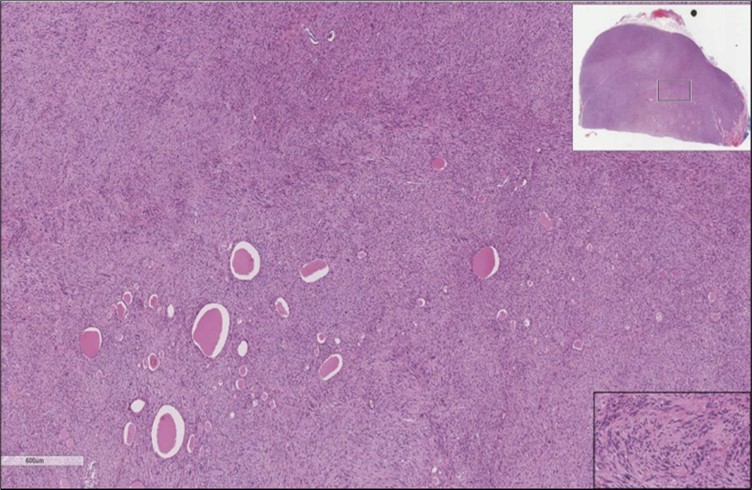

When diagnosing thyroid swelling, imaging studies have been helpful in differentiating malignant from benign tumors with US being used as an initial evaluation tool when assessing thyroid nodules. Tumors are categorized based on composition, echogenicity, shape, margin and echogenic foci into added scores determined by the TI-RADS system, which determines the need for FNA 13. Other imaging modalities include MRI and CT. However; radiological assessment does not distinguish between the types of thyroid cancer, and therefore FNA and biopsy are of crucial importance 3, 6. On a pathologic sample, LMS appears as spindled eosinophilic cells with elongated blunt-ended or cigar-like nuclei arranged in fascicles 2, 7 (Figure 1, Figure 2, Figure 3). Despite the unique microscopic morphology, LMS cannot be distinguished from other spindle cell tumors such as spindle cell variant of medullary thyroid cancer, anaplastic thyroid

Figure 2.Left thyroid On a Higher power, few thyroid follicles are noted and the lesion is composed of spindle cells with sweeping fascicles (H&E, ×200).

cancer, or other metastatic tumors without further testing with genetic or molecular studies 3, 7. Immunohistochemical testing plays a vital role in differentiating LMS from such similar tumors as it stains positive for vimentin and smooth muscle actin (SMA), and is variably positive for HHF35, desmin (50%-100%), and H-caldesmon 3, 6. Moreover, there were no reported cases where thyroid LMS stained positive for thyroglobulin, cytokeratin, calcitonin, chromogranin, or protein S100 3. Our patient’s left thyroid biopsy showed the characteristic microscopic features and was positive for SMA, desmin, caldesmon, P63 with patchy EMA (Figure 1, Figure 2, Figure 3, Figure 4) as well as her liver biopsy (Figure 5, Figure 6, Figure 7); whereas her right thyroid showed clear papillary thyroid cancer cell features (Figure 8, Figure 9).